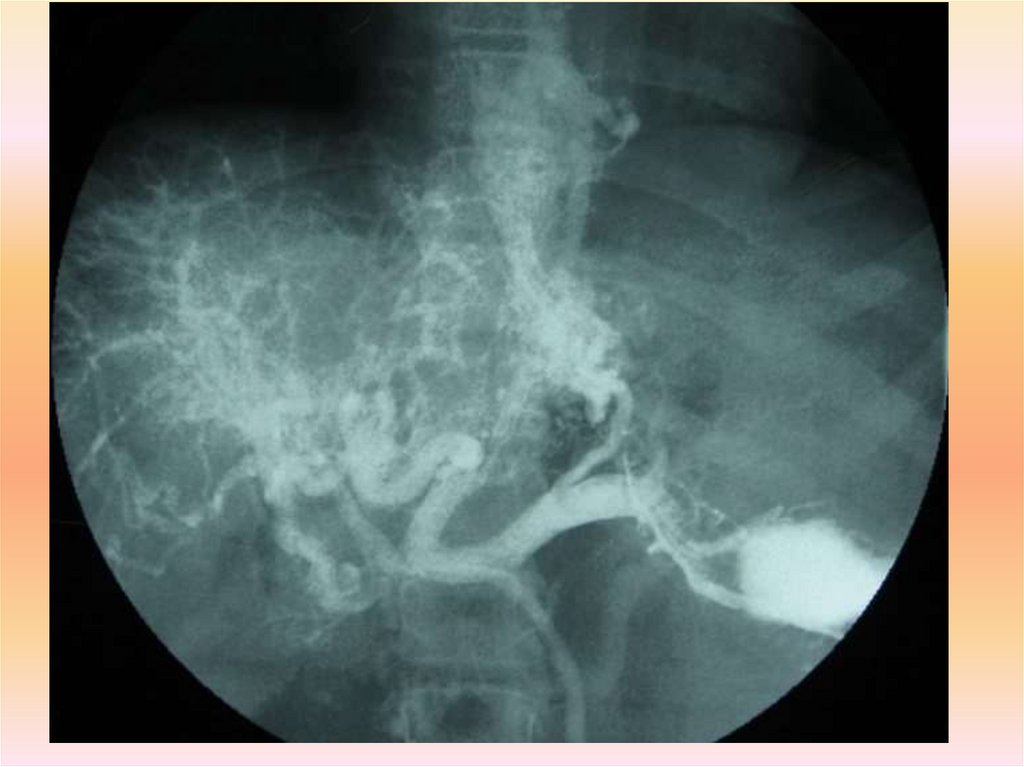

Если и это (-) ,можно думать, что источник кровотечения, скорее всего,

расположен в тощей или подвздошной кишке. В этом случае

выполняют контрастное исследование тонкой кишки

(энтерографию) или селективную мезентерикографию.